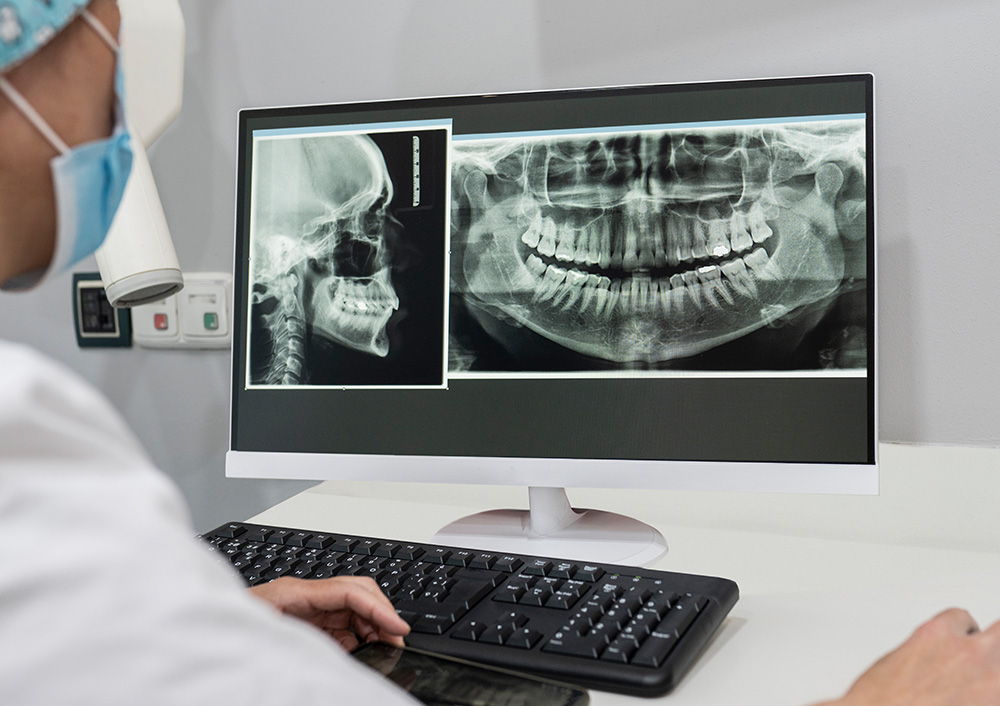

디지털이기 때문에 가능합니다.

모의 수술과 수술 후 결과까지 예측하는

최소식립 전악임플란트

최소식립 전악임플란트는 칼로 잇몸을 절개하는 방법이 아닌 임플란트 식립 부분만 작은 홈으로 구멍을 뚫어 시술하는 방법입니다. 이 치료 방법은 수술 후 통증이나 붓기, 출혈이 거의 없어 부담이 없는 수술입니다.

기존의 절개 수술에 비해 수술 시간이 짧고 병원 내원 횟수가 적어 연세가 많으신 고령의 환자 또는 당뇨와 고혈압 같은 전신 질환이 있으신 분들도 안전하게 시술하실 수 있어 최고의 정확성과 안정성을 보장하며 부작용을 최소화합니다.